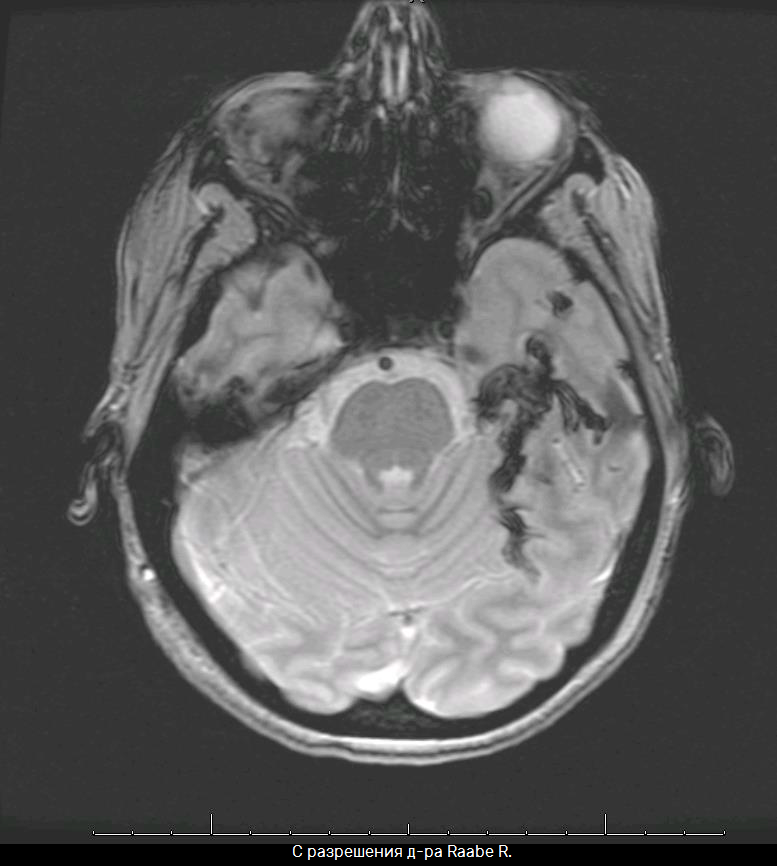

КЛЕЙ УЖЕ ИСПОЛЬЗУЕТСЯ ДЛЯ ЛЕЧЕНИЯ АВМ

ДОСТАВКА ЧЕРЕЗ МИКРОКАТЕТЕР

✱С разрешения д-ра Raabe R.

Большое количество клея / тромба

остаётся в АВМ, изображение МРТ

"Если мы можем склеить высокопоточные церебральные АВМ, почему бы не склеивать низкопоточные варикозные вены?"

Dr. Raabe R., 2008